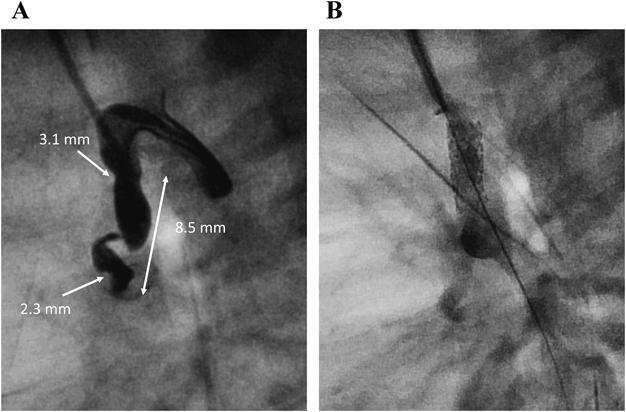

症例1は,PA/VSD,奇形症候群に伴う多発形成異常があり,肺低形成や緊張性気胸,肺出血の合併から人工呼吸管理を要し,腎低形成による代謝性アシドーシスの補正が困難で腹膜透析を導入していた.プロスタグランジン製剤に不応の動脈管の狭小化を認めたものの,開心術のリスクが高い基礎疾患と判断し,生後2か月,体重3.6 kgでDSの方針とした.右総頸動脈をカットダウンでアプローチし,屈曲したPDAにDriver™ 3.0×9.0 mm(Medtronic Inc; Santa Rosa, CA)を留置した.肺動脈側へステント位置がずれ,スネアで修正困難だったため,Driver™ 3.0×12.0 mm(Medtronic Inc; Santa Rosa, CA)をstent in stentで追加したところ,動脈管全体をカバーすることができた(Fig. 2).その後の経過は良好で,生後6か月でRastelli手術に到達し,腹膜透析下に退院した.

Pediatric Cardiology and Cardiac Surgery 36(4): 294-305 (2020)

Fig. 2 Case 1: DS for PA/VSD, lung and renal hypoplasia

A) Lateral view of ductus arteriosus angiography revealed almost vertical and originating from transverse aortic arch. B) Angiography after DS. PA/VSD: pulmonary atresia/intact ventricular septum